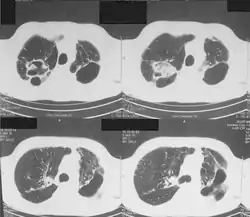

Mycobacterium heckeshornense- Chest computed tomographic scan showing pulmonary infiltrates and cavities.

- Seems to be pathogenic in immunocompetent humans.